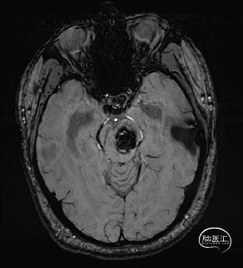

术前MRI检查

术前MRI检查提示左侧丘脑中脑海绵状血管瘤并卒中,梗阻性脑积水;

诊断:1.左侧丘脑中脑海绵状血管瘤并卒中,2.梗阻性脑积水;

年轻患者,较短时间内发生左侧丘脑二次出血,出现右侧面部及上肢麻木,复视,第二次出血后并发梗阻性脑积水,出现头痛。结合病史、神经系统体征、头颅CT及MRI检查,诊断左侧丘脑及中脑CM并卒中、脑积水明确,并导致了神经功能障碍,具备手术指征。

脑积水导致的颅内高压,幕下小脑上通路更为狭小,大脑大静脉复合体的显露及分离困难增大;

根据MRI及DTI显示,只有在丘脑与上丘之间的点(dot)进入病变才可能在切除病变时最大程度保护神经功能,由于上述原因,该“点”在术中显露极其困难,虽有导航指引,电生理监测的条件下,对术者的耐心、技术、经验及体能依然是极大的挑战;